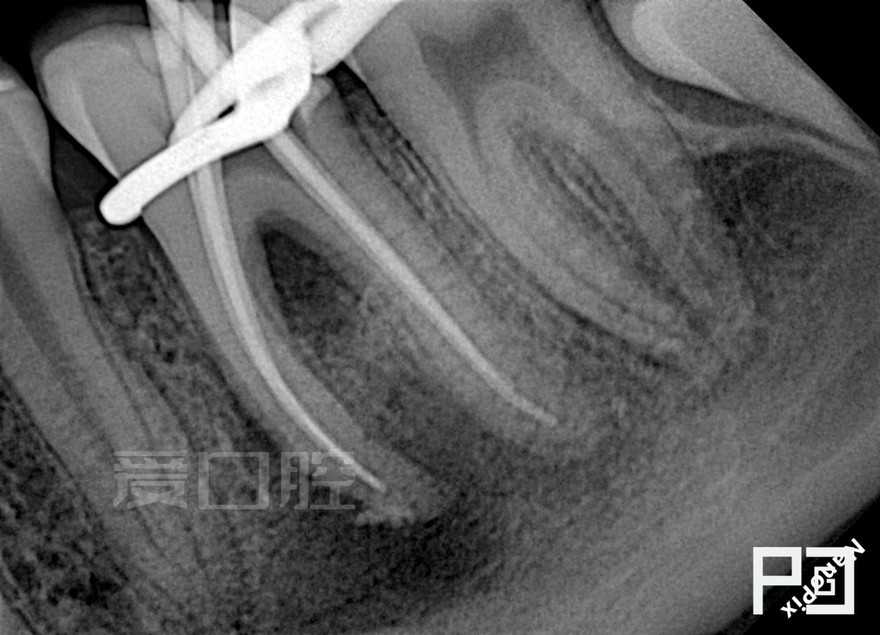

看个根充 —— 下6

by Paco CG